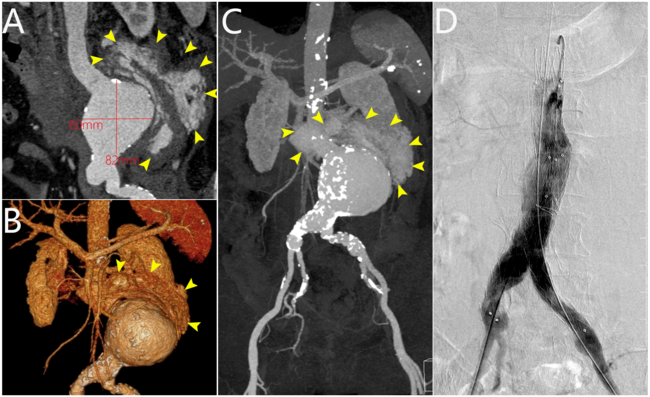

Stents to the Rescue: Battling a Ruptured Abdominal Aneurysm

Video Supplement to "Stents to the Rescue: Battling a Ruptured Abdominal Aneurysm" (Clinical Image).